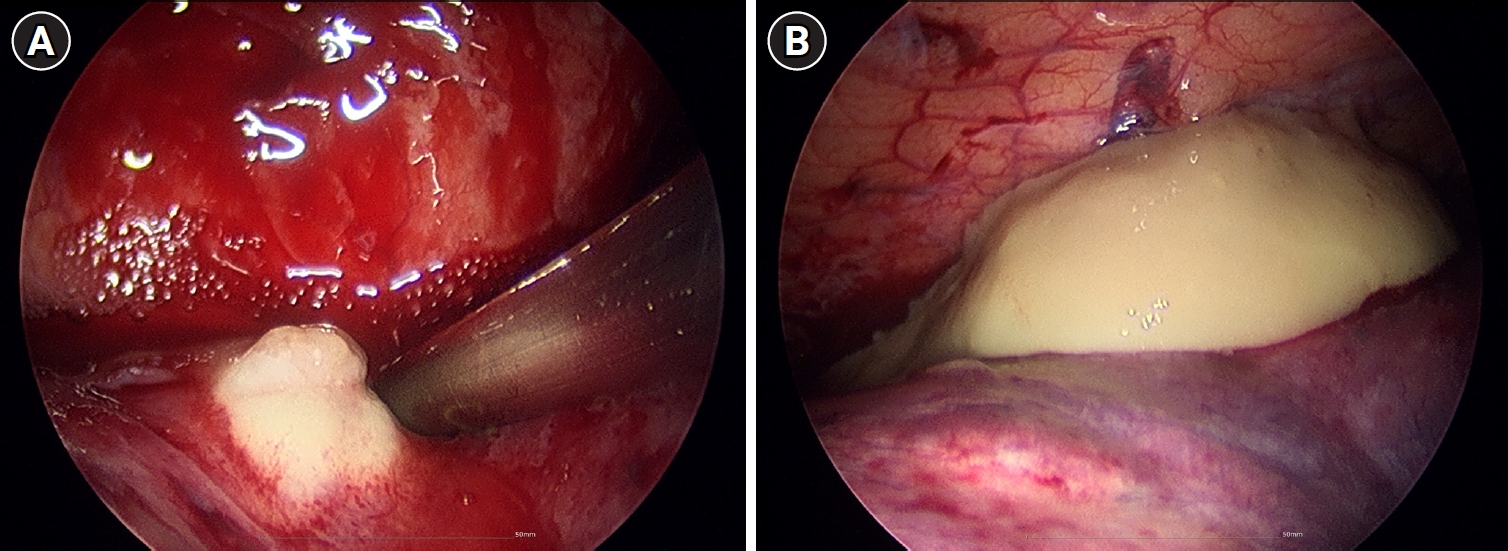

Upon admission, his vital signs were as follows: blood pressure, 100/60 mmHg; pulse rate, 120 beats/min; respiratory rate, 20 breaths/min; and body temperature, 38.2°C. Pulse oximetry revealed that oxygen saturation was 95% on room air. Chest auscultation revealed crackling rales in the lower bibasilar lobes. Initial laboratory investigations showed significant leukocytosis with white blood cell (WBC) count of 28,100 cells/µL and elevated C-reactive protein (CRP) level of 35.39 mg/dL. To evaluate for potential secondary infection, multiple microbiological cultures were performed during the early hospital course. These included blood and sputum cultures on the day of hospital admission (day 1), a follow-up sputum culture on day 2, and sputum and urine cultures on day 3. All cultures yielded no specific growth. Chest radiography revealed bilateral pleural effusions and patchy consolidations in both lower lung fields suggestive of pneumonia (Fig. 1). Contrast-enhanced computed tomography (CT) of the chest revealed ground-glass opacities in the right middle lobe, base of the right lower lobe, and left lower lobe, accompanied by intrinsic air and bronchovascular bundles. Based on these findings, the patient was admitted to the intensive care unit with a diagnosis of encapsulated necrotizing pneumonia.

Fig. 1.

Initial chest radiograph showing bilateral patchy consolidations over lower lung fields with pleural effusion.

Fig. 1. Initial chest radiograph showing bilateral patchy consolidations over lower lung fields with pleural effusion.